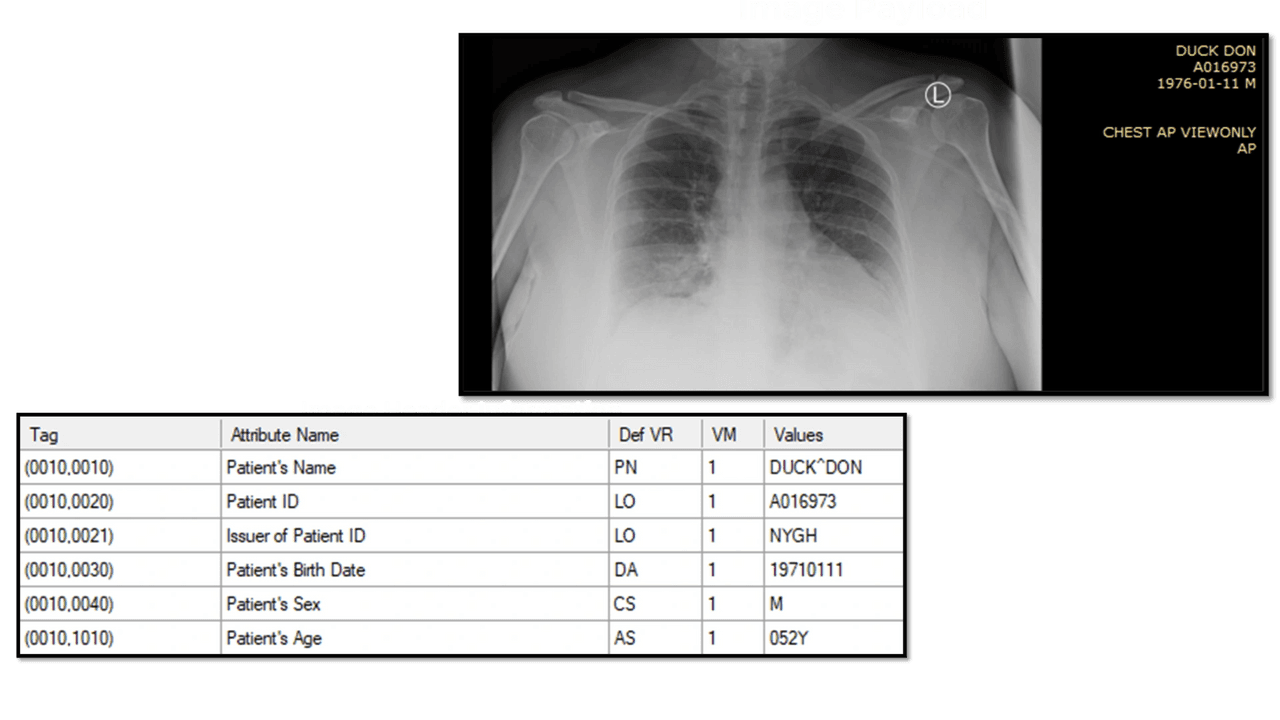

The DICOM Header: Your Guide to the Contents

Much like the detailed labels on a shipping container, a DICOM file’s payload is carefully enclosed within a digital 'container.' On the exterior, a DICOM header serves a similar function to a container's handling instructions and labels. This header conveys crucial data, guaranteeing that the image's meaning, context, encoding, and additional critical details are recorded with precision. The header does more than simply present the image; it narrates the journey from its creation to its final destination, weaving in the patient's story and ensuring the image is more than a picture — it's a chapter in a medical narrative.

Inside the DICOM File: Unveiling the Payload

Now, let's peek inside. Beyond the header lies the actual DICOM payload. It's not just an image; it's a constellation of pixels, each carrying a fragment of a larger story about a patient's health. This is what the medical professionals are after - the 'goods' that the DICOM standard safeguards and delivers.